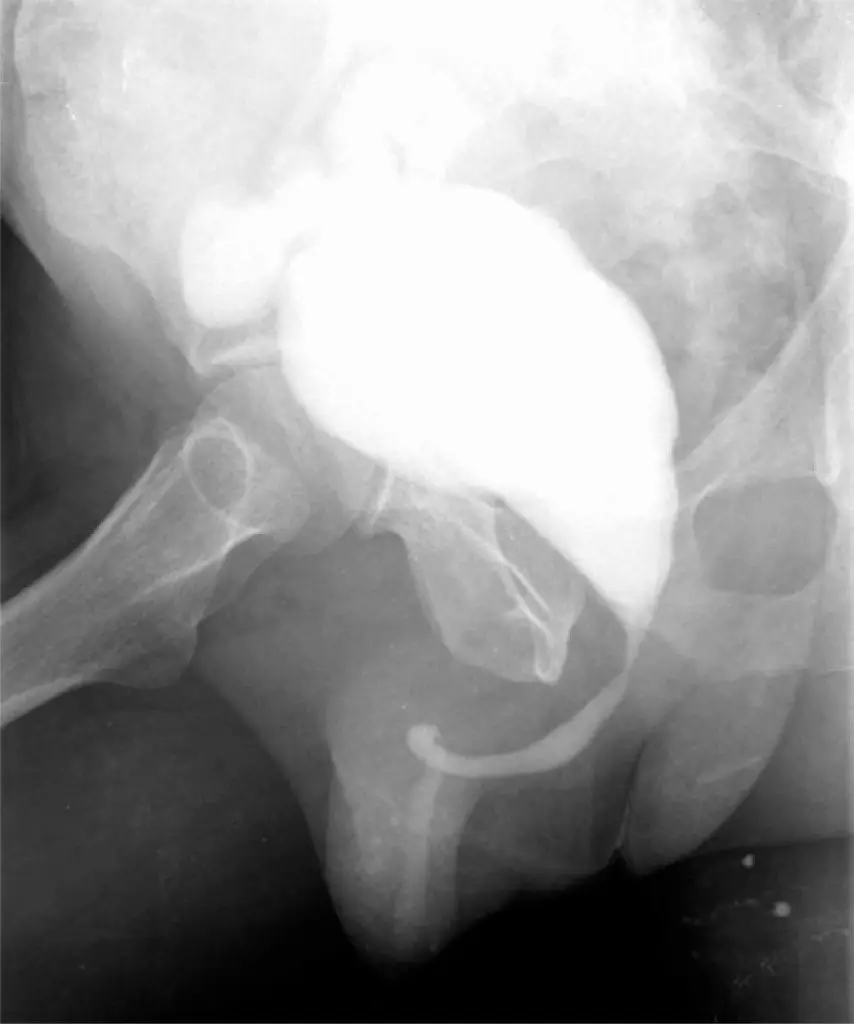

Cistectomia com reconstrução de neobexiga ortotópica ileal para tratamento de bexiga contraída após aplicação de bacilo de Calmette-Guérin intravesical

O câncer de bexiga é um importante problema de saúde mundial, tanto pelas elevadas taxas de prevalência, quanto pelos custos relacionados ao tratamento. Desde a introdução da imunoterapia intravesical adjuvante com bacilo Calmette-Guérin, vem sendo observada diminuição na taxa de recorrência. As principais complicações são de pequeno porte e simples resolução a partir de medidas locais e orientações. A bexiga contraída, uma complicação local rara e grave, mas incapacitante em alguns casos, é observada principalmente em doentes com um programa de manutenção. Relatamos aqui o caso de um paciente masculino submetido a ressecção transuretral da bexiga por um carcinoma urotelial T1 de alto grau, que desenvolveu tal complicação durante tratamento com bacilo Calmette-Guérin, sendo portanto submetido à cistoprostatectomia com realização de neobexiga ortotópica ileal.